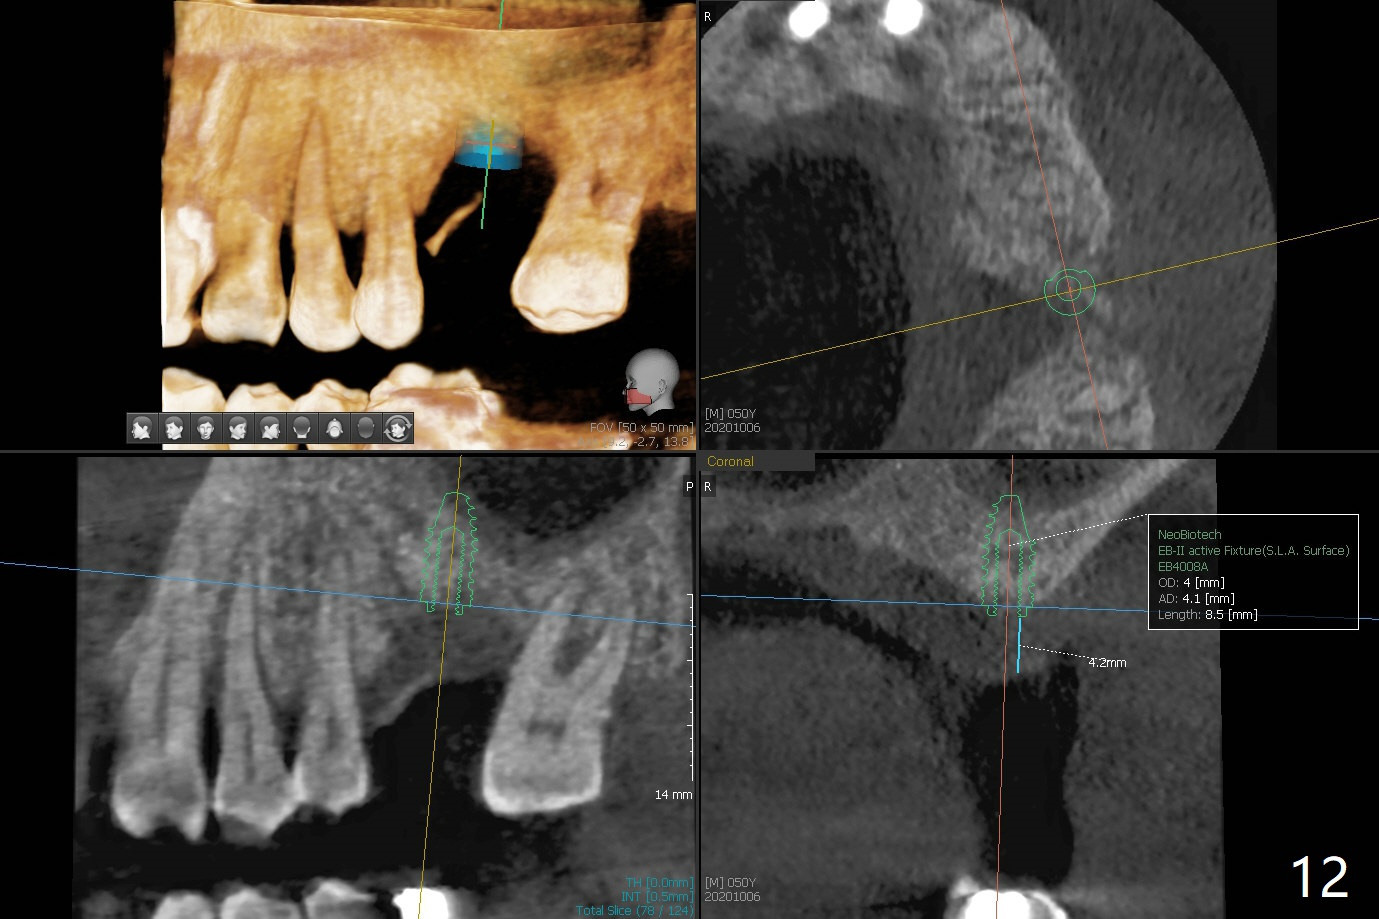

50岁男两年前不肯拔牙左上6(图一),现在要求及早拔除植骨(图二),几个月后与左下7一起植牙。我们准备深洗(图三橘黄色)后拔除残根(黑色),翻瓣后植入粘性骨块(红色)。为了解释手术步骤,给牙槽骨(A)做冠状切面,如图四黑色四方形,B:颊侧;P:腭侧;而粉红色代表牙龈(G)。图五红线表示切口,弯箭头:翻瓣,如图六。然后植入粘性骨块(图七:S)。盖上PRF膜(图八蓝线)以及不可吸收膜(图八绿线),最后使用PTFE缝线(图九:黑线)稍微关闭伤口,不至于压扁骨块。这样可行吗?需要使用tenting screw防止骨块塌陷?为了避免使用后者,索性直接植入植体(图十:绿色)和基台(浅蓝色),周围堆放骨粉(红色)。覆盖PRF膜(图十一:深蓝色),缝合(细线)。骨密度1200-1400单位;骨粘膜厚度4.2毫米,血供好(图十二;图十三:G: 牙龈)。翻瓣(图十四:箭头),植入植体(绿色),放置基台(粉红色)和骨粉(红色)。由于基台占据空间,缝合应该是松弛的,下面骨粉不易移位,在暴露螺纹附近愈合。Jennifer: flap surgery; since osteotomy will be created in a slope with most likely distal deviation, design the long axis of the implant mesial by 1 mm occlusally.

No Deviation 手术 提升 Xin Wei, DDS, PhD, MS 1st edition 09/29/2020, last revision 04/04/2021